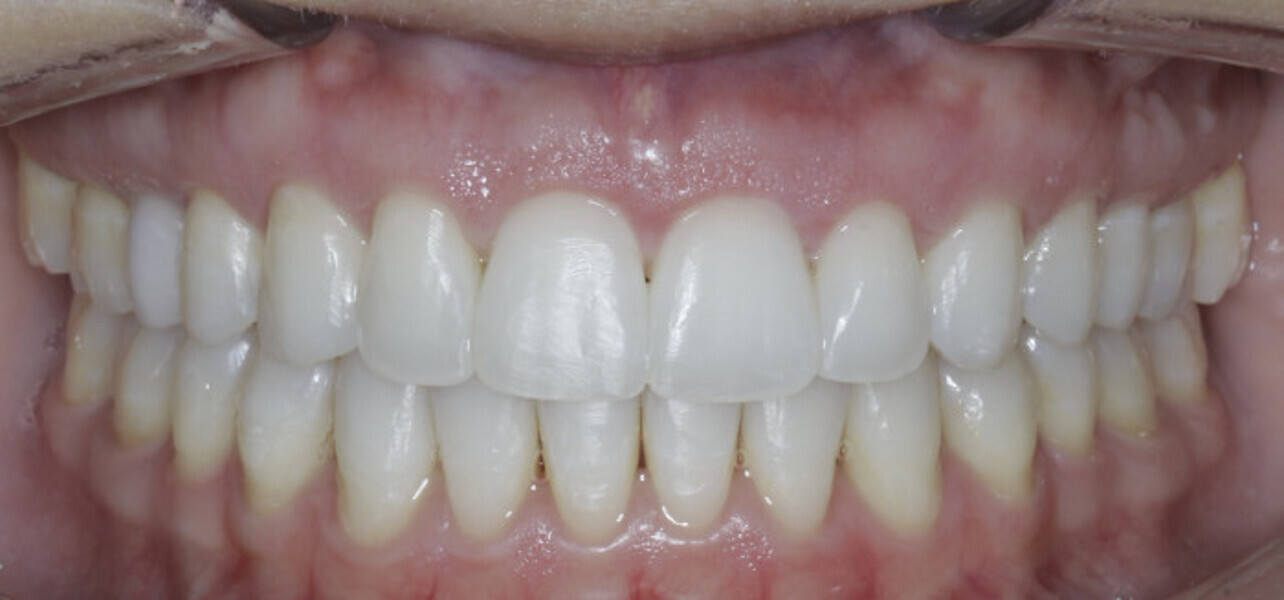

New Age orthodontics and orthopaedics with temporary anchorage devices